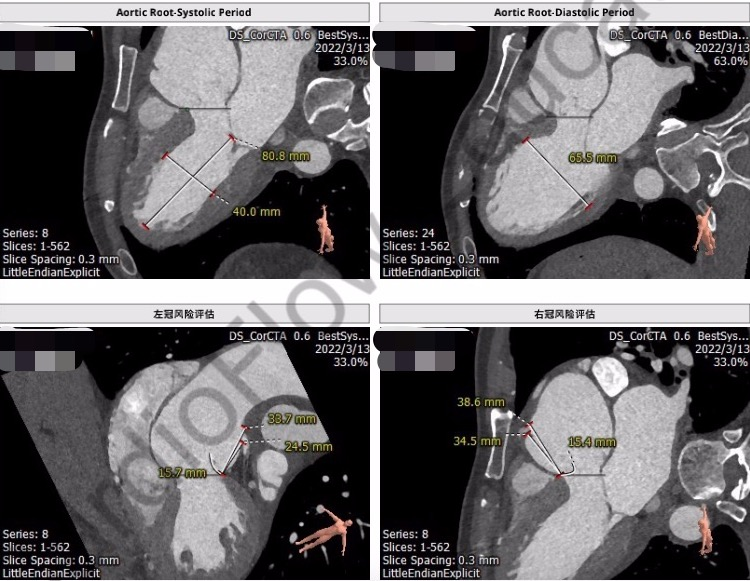

CT分析

主动脉根部解剖:

钟炜主任指出:患者为三叶式主动脉瓣纯反流病例,瓣环周长84.1mm,平均径26.4mm。LVOT周长83.2mm,平均径26.5mm。瓦氏窦瘤样扩张,窦宽大于50mm,窦管结合部几近消失,锚定能力严重不足,该患者选择TAVR手术,瓣膜支架能否在这么大的窦瘤和瓣环内固定是非常有挑战的,通过详细分析CT结果,如果能将瓣膜支架放在主动脉瓣下4-5mm,应该能够充分利用径向支撑力起到固定作用,为了精准释放瓣膜支架,建议经颈动脉入路。